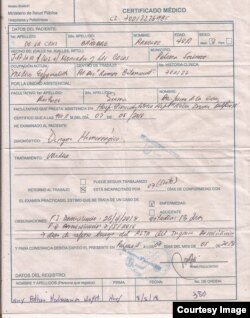

El médico explicó que a partir del 26 de abril se le presentó un cuadro febril que se extendió por cinco días hasta el 30 de abril.

Al quinto día la fiebre cedió y mejoró su apetito. Pero a la semana comenzó a sangrar al cepillarse los dientes, fue revisado por su hijo estomatólogo quien determinó que se trataba de un empeoramiento de una dolencia dental.

"Mi hijo que es estomatólogo me examinó y pensó que se trata de una gengivitis y comencé a hacer tratamiento para eso", explicó.

Pero el día 2 de mayo se agudizó el sangramiento y le brotaron manchas rojas en las piernas, así que su esposa que es técnico de laboratorio, le practicó análisis.

"Tenía una infección viral y las plaquetas estaban bajas", dijo. "Consideré que podía ser portador de un dengue hemorrágico y solicité auxilio de un colega clínico en el cual confío y después de examinarme me dijo que concordaba con el diagnóstico que yo me había hecho".

Tras conformar el diagnóstico se presentó en la unidad de cuidados intensivos del municipio Palma Soriano, donde lo ingresaron por indicación de un médico que identificó como Quintela.